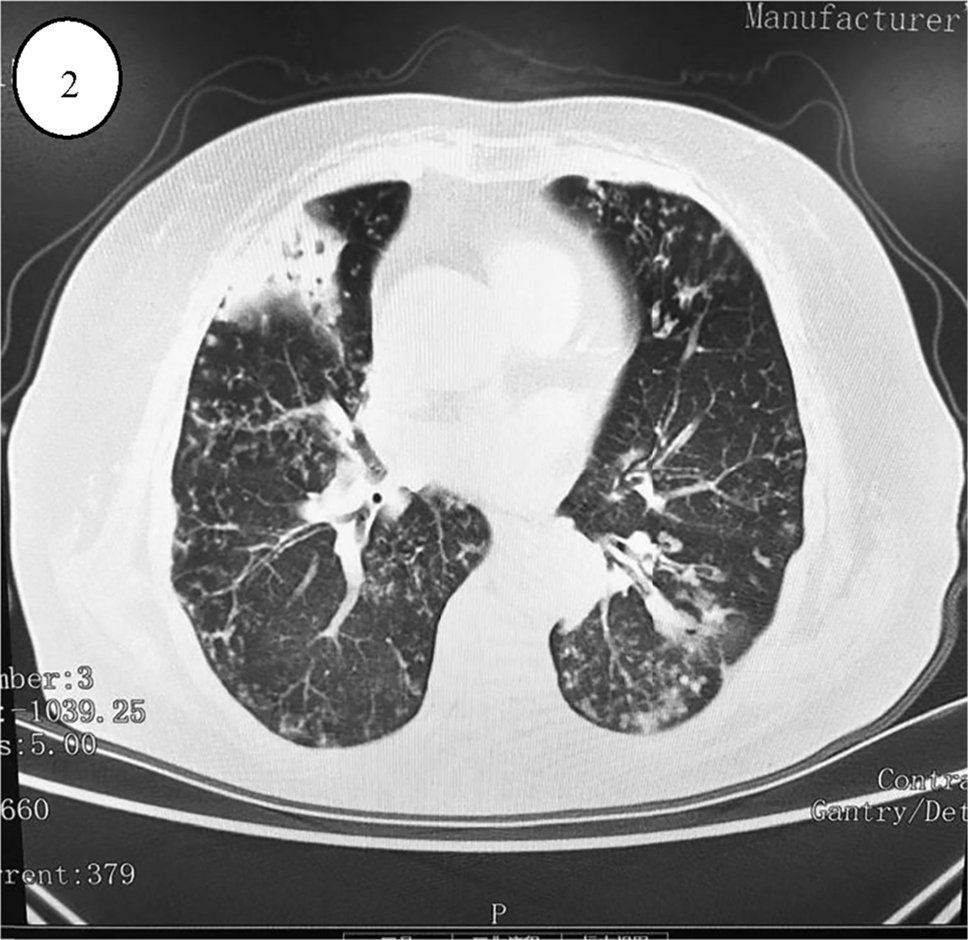

A 72-year-old female patient experienced a height reduction of 10 cm over 10 years and presented to our outpatient clinic in early November 2023 with severe back pain after an unstable standing twist. She had a history of coughing and sputum production for over 30 years, menopause at 49, and no other medical history. The patient's back pain and bilateral rib pain gradually worsened over a week, becoming more pronounced during activity and coughing, and alleviating with rest. Physical examination revealed: height 158 cm, weight 52 kg, visible spinal deformity, reduced chest-abdominal wall distance, and a bow-shaped kyphosis on spinal examination. Lung auscultation revealed moist rales. MRI indicated: 1. Fresh compression fractures of T9-11, with bone marrow edema changes in the T9 lamina; 2. Compression fractures of L1, 2, 4 (old); 3. Disc protrusion at L3/4, L4/5, and Schmorl's nodes formation at L1-4; 4. Osteoporosis of the thoracolumbar spine; thoracolumbar degenerative changes; subcutaneous fasciitis of the back as shown in Fig. 1. Dual-energy X-ray absorptiometry indicated: L1-4 bone density 0.560 g/cm2, T-score -4.4, Z-score -1.5, representing severe osteoporosis. To determine the cause of the patient's osteoporosis, serum levels of calcium, phosphorus, and parathyroid hormone (PTH) were checked: calcium, 1.85 mmol/L; phosphorus, 0.83 mmol/L; PTH, 81.20 pg/mL, all within normal ranges. Additionally, tests showed white blood cells, 5.22*10^9/L; red blood cells, 3.88*10^12/L; hemoglobin, 111 g/L; C-reactive protein, 3.33 mg/L; 25-hydroxyvitamin D, 16.30 ng/mL; thyroid-stimulating hormone (TSH), 1.2729 μIU/mL; urea, 4.47 mmol/L; creatinine, 41.2 μmol/L; aspartate aminotransferase, 20 U/L; alanine aminotransferase, 17 U/L; all immune series negative, ruling out hyperparathyroidism, hyperthyroidism, liver dysfunction, kidney dysfunction, and immune series diseases. Given her 30-year history of coughing and sputum production, a chest scan was completed, and paranasal sinus scan indicated: left maxillary sinusitis, slight deviation of the nasal septum, possible chronic bilateral otitis media; multiple small nodules in both lungs, slightly enlarged mediastinal lymph nodes; osteoporosis, uneven bone density of the manubrium, fracture of the left second anterior rib, sternal fracture, compression fractures of T6, L9, L10. She had a 30-year history of persistent coughing and sputum production, with paranasal sinus CT indicating chronic sinusitis, chest CT showing diffuse small nodular shadows as in Fig. 2, lung auscultation with moist rales, diagnosed as diffuse panbronchiolitis (DPB). After ruling out secondary factors and common pathogenic factors, it was suspected that her severe osteoporosis might be closely related to diffuse panbronchiolitis, and whether DPB could induce or exacerbate osteoporosis. Based on this hypothesis, the patient was treated with anti-osteoporosis and anti-inflammatory medications. Currently, her pain has alleviated, and she can perform daily activities, but she remains under continuous treatment.

Fig. 2

Chest CT showing diffuse small nodular shadows in the lungs